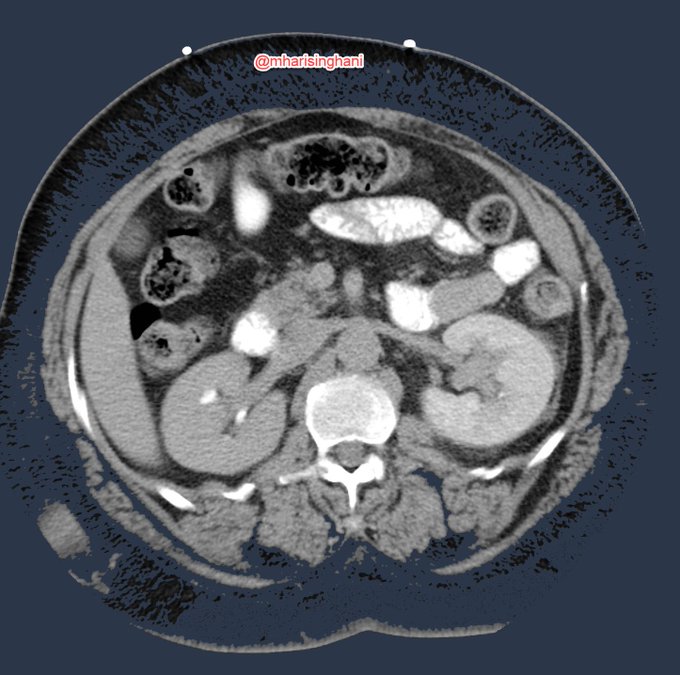

Calcified mesenteric mass; is this carcinoid metastases, treated lymphoma or retractile mesenteritis; biopsy showed carcinoid metastases